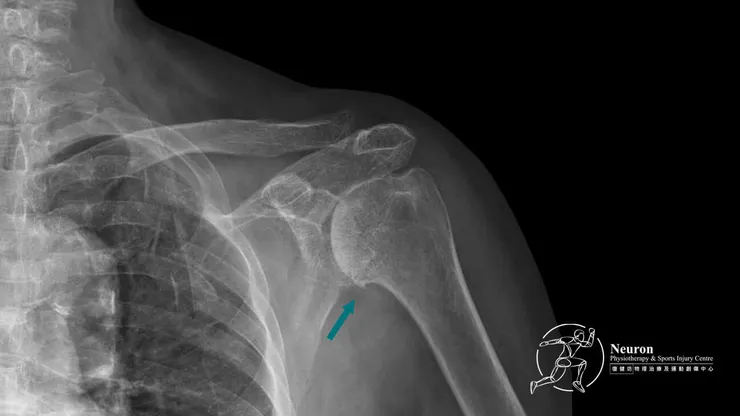

在診斷階段,Neuron 復健坊的專業團隊會運用先進的影像學檢查技術,如X光、MRI等,精確地定位骨刺的位置和程度。骨刺根據檢查結果,治療師會為患者量身定制一套個性化的治療方案。骨科物理治療這套方案通常包括物理治療、運動療法以及必要的藥物輔助。